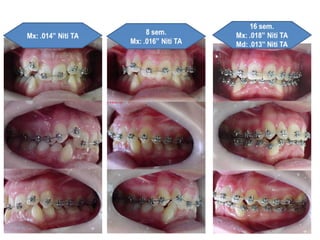

1)N/A (arcos red. NiTi TA)

2)2 mm de Desgastes

interproximais 33 a 43

3)Arcos ret. Niti

4)Intercuspidação

5)Finalização (arcos ret. Aço

inox.)

6)Remoção e Contenções